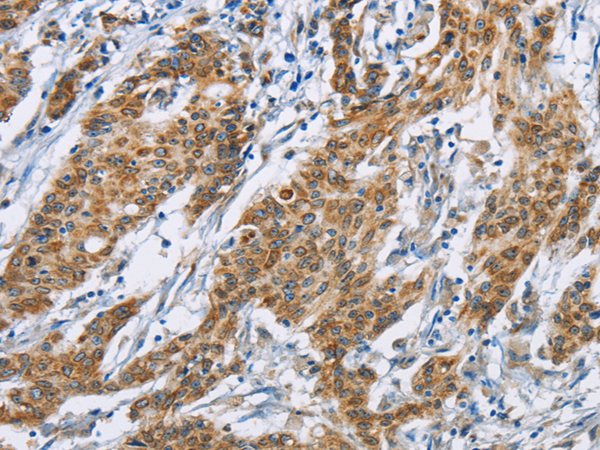

分类: 科研抗体货号: P08131别名: CD329; CDw329; FOAP-9; siglec-9; OBBP-LIKE应用: WB,IHC反应种属: Human